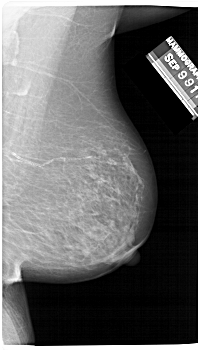

A_1481_1.RIGHT_CC

RIGHT_MLO LINES 6646 PIXELS_PER_LINE 3751 BITS_PER_PIXEL 12 RESOLUTION 43.5 NON_OVERLAY